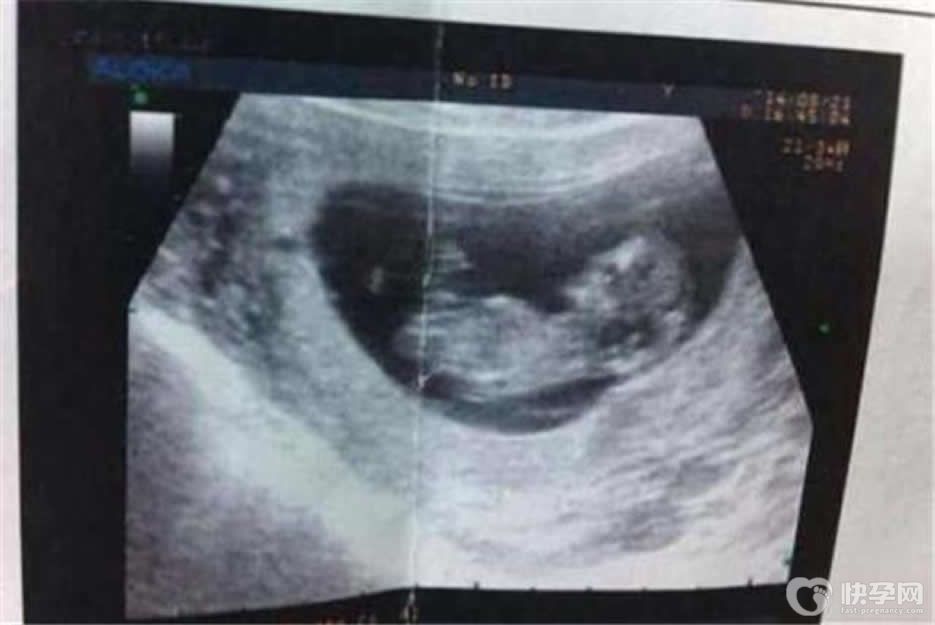

21周b超男女腿部间的区别图分享,亮点白线揭晓性别秘密

众所周知,胎儿的性别需要通过B超检查才能够准确判断,但是由于我国禁止非医学需要的性别鉴定,因此在怀孕21周的时候做B超检查医生是不会告诉家长孩子的性别的。但其实这个..

30周b超男女腿部间的区别图 真实b超图片

一般来说,怀孕除了要注意生活中的方方面面之外,为了更好更直观的监测到胎儿各个孕周的发育情况,就需要通过产检来看了。在怀孕3个月的时候会做第一个重要的产检,就是nt..